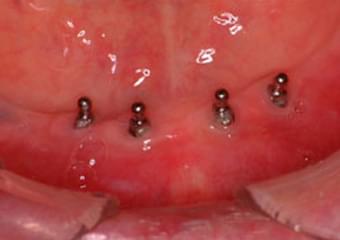

義歯の維持装置ためのインプラントを4本埋入した状態